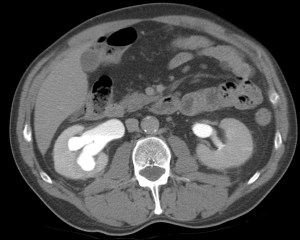

CASO CLÍNICO: Recopilatoción.

Paciente de 59 años con antecedentes personales de Cá de vejiga.

Se le realiza una Uro-Tc por seguimiento al año, aunque en esta ocasión el paciente refiere episodio de hematuria.

Tras el tratamiento de la recidiva y nefrostomía para la hidroureteronefrosis, vuelve acudir al hospital a los 9 meses por episodio de dolor en FD y malestar general. Se realiza una ecografía de urgencias.

Se realiza nueva TC bifásico abdominopélvio y Uro TC.

- Paciente con numerosas recidivas por Cá vejiga.

- Ha desarrollado un tumor metacrónico en pelvis renal derecha, también responsable de la hidroureteronefrosis.

- Mala evolución radiológica del proceso a expensas de metástasis pulmonares y hepáticas.